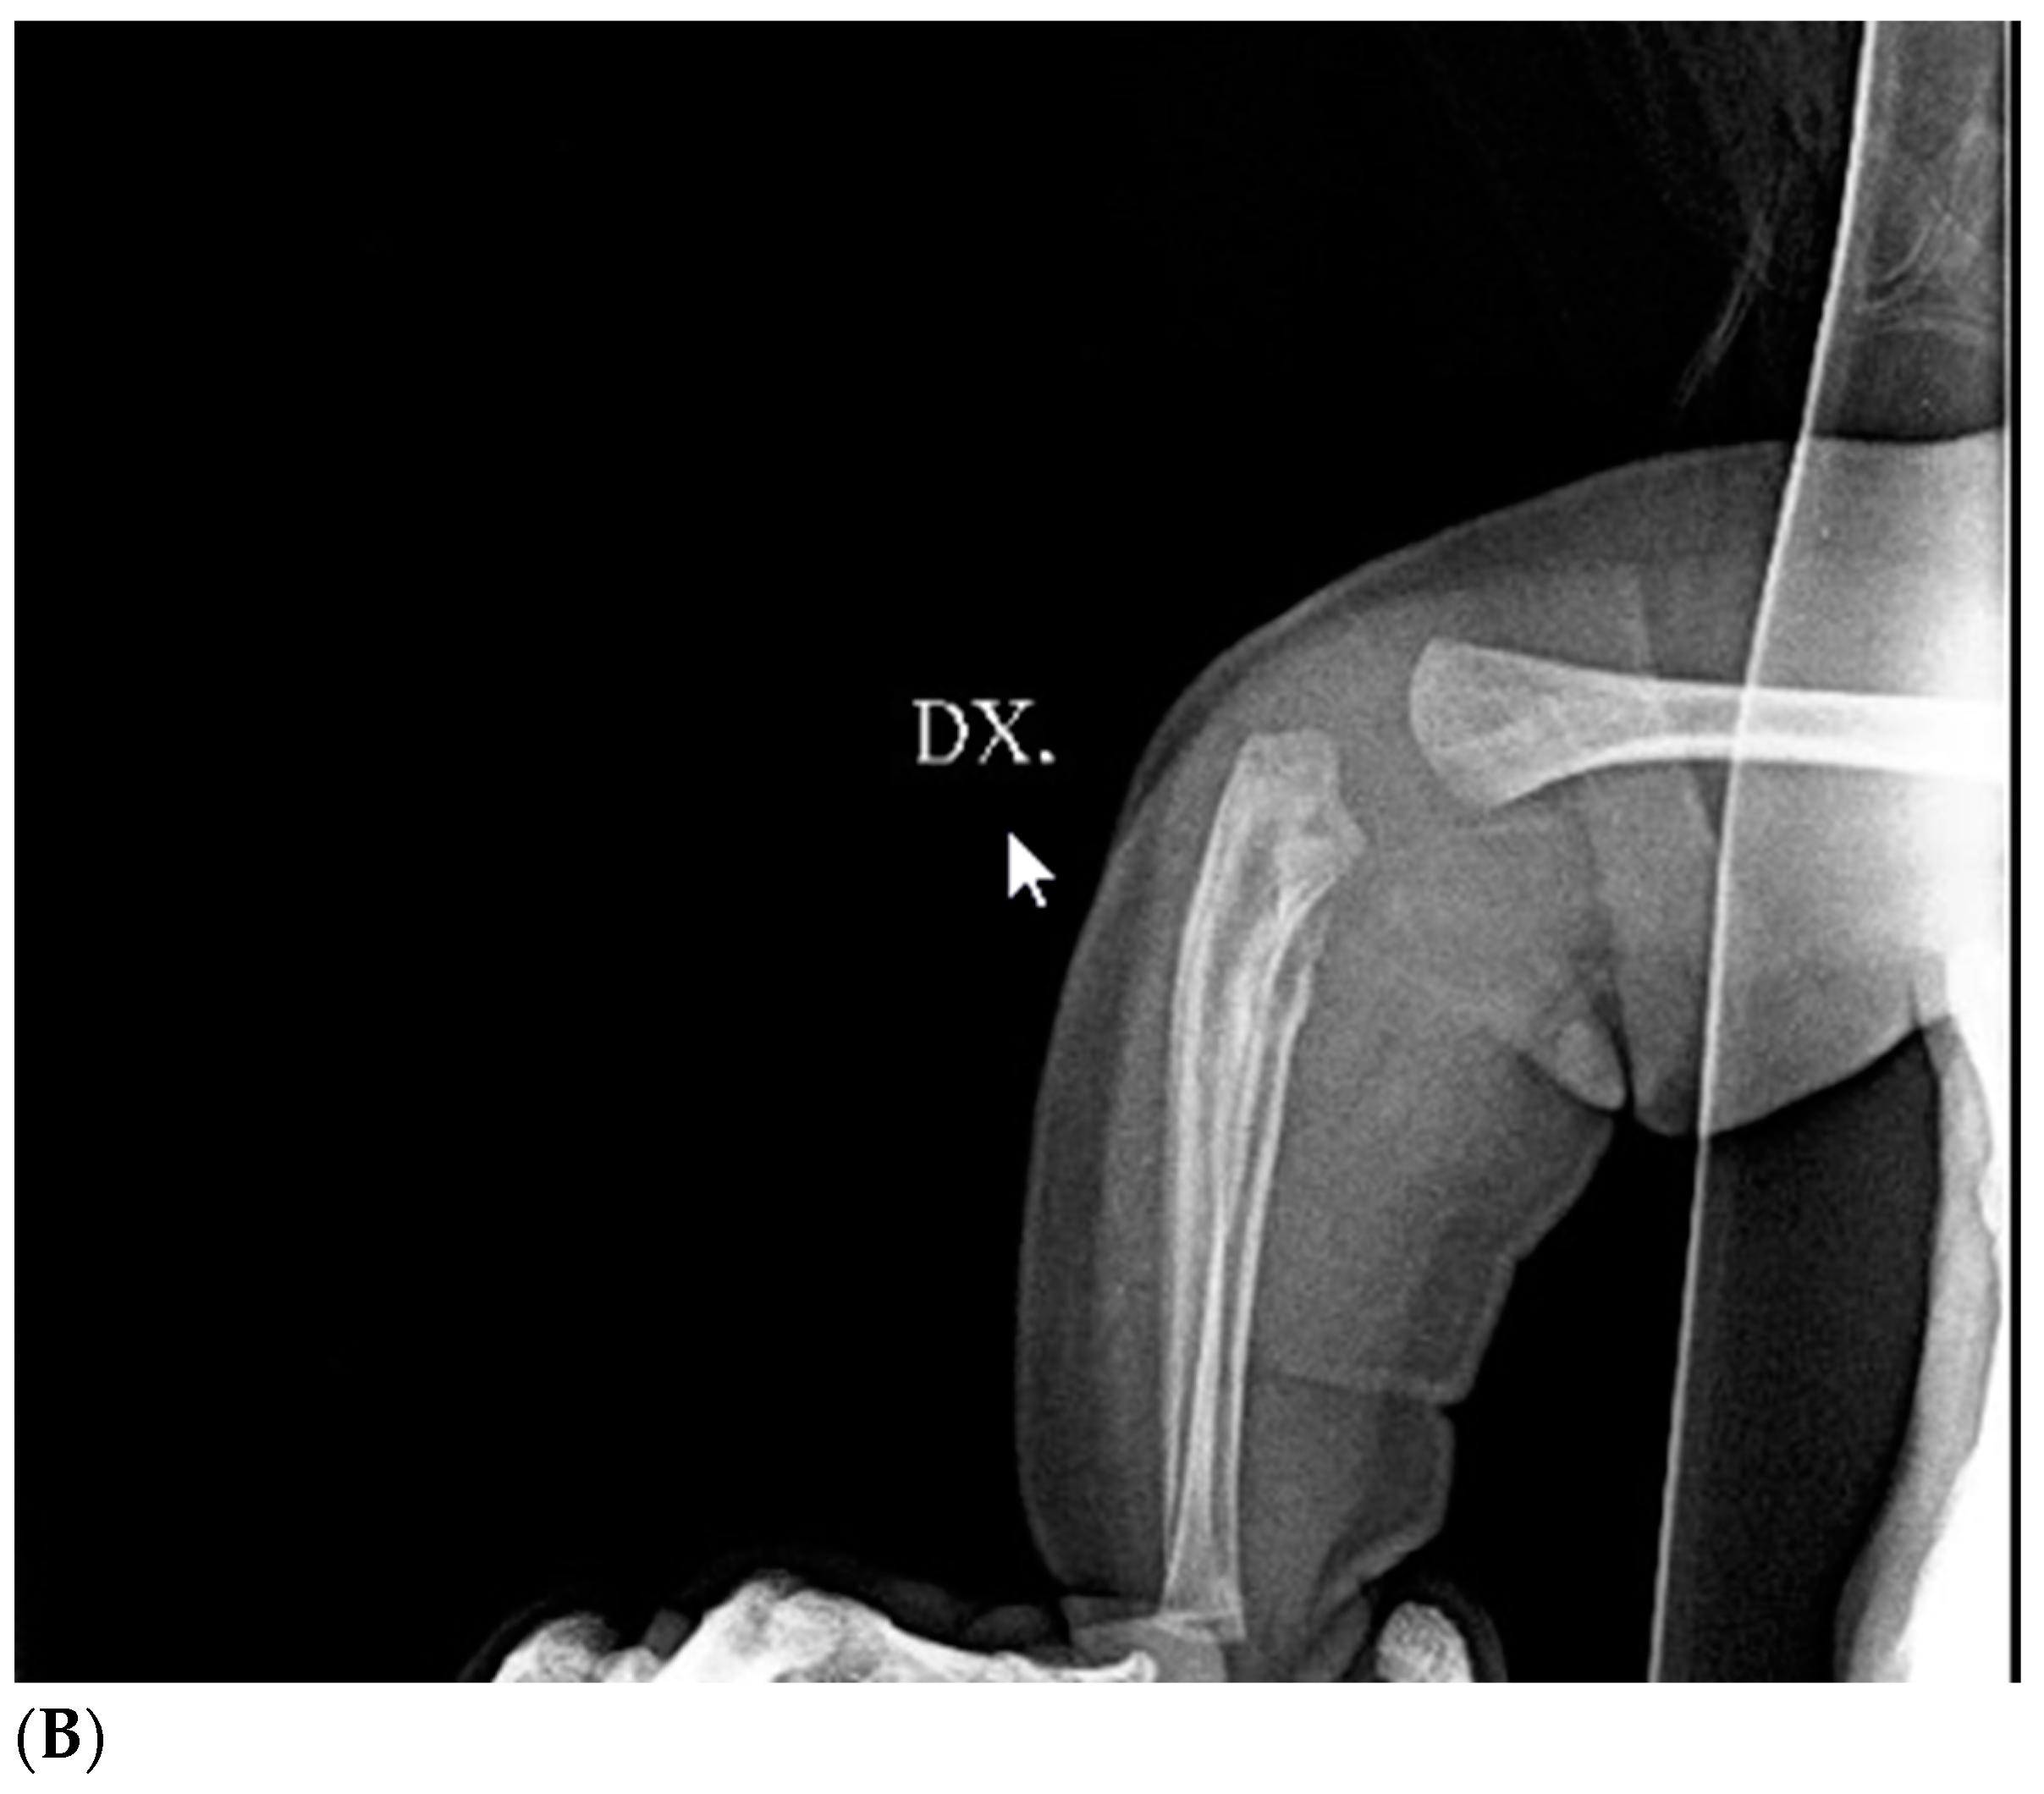

Brain ultrasound performed after birth was normal. Blood tests were negative for infectious diseases. Complete blood count, calcium, glycemia, lipid profile, and urine test were normal, and tumor markers were negative. The first diagnostic hypothesis was shaft fracture of the right humerus, but X-ray of the right arm and forearm was negative. Ultrasonography showed a solid, slightly vascularized lesion with a hyperechoic center and a surrounding ring, involving brachial muscle, compatible with intramuscular hematoma, which caused compression of the radial nerve (Figure 1). Studies on nerve conduction revealed that radial motor compound muscle action potential (CMAP) and radial sensory nerve action potential (SNAP) had significantly reduced amplitude distal to the elbow. A watchful, waiting attitude with physiotherapy was performed. The newborn had benefited from passive movement-type physiotherapy sessions and sensorimotor facilitation for upper limb integration. The patient was also fitted with a custom-designed static splint made of thermo-moldable plastic that had perforations, immobilizing only his right wrist and fingers in a neutral position (Figure 2). Thankfully, there were no signs of contractures or stiffness in the wrist or any of the finger joints. At 2 months of life, a second X-ray showed proximal radius deformity, due to a solid mass compression (Figure 3A,B). Magnetic resonance imaging of the right upper limb revealed a solid, hypovascular mass with an area of necrosis infiltrating and involving the radial head, and fatty atrophy in line with proximal extensor muscle denervation alterations. The mass was mildly hypointense on T1-weighted sequences and hyperintense on T2-weighted images, with mostly peripheral post-contrast enhancement (Figure 4A,B). Total body MRI scan made it possible to evaluate the presence of similar lesions in other parts of the body, so to exclude diagnosis of infantile myofibromatosis. CT angiography of the right upper limb was performed to evaluate upper extremity arterial abnormalities and it showed regular patency of arterial vessels, with dislocation of the brachial artery by the mass. The main differential diagnosis included fibrous hamartoma of infancy, juvenile hyaline fibromatosis, infantile fibrosarcoma, or Ewing sarcoma/primitive neuroectodermal tumor. A fine needle biopsy of the lesion confirmed that it was a benign mesenchymal tumor compatible with myofibroma. Genetic testing revealed no familial inheritance. Following physiotherapy, with the same activity improving with taping for the wrist and fingers’ extension, then replaced by a Lycra dynamic orthosis (flexa) (Figure 5) during 3–4 h when awake and stretching exercises, an improvement in the infant’s right arm motility was seen within 4–5 months of birth, but no activation of the wrist and finger extensors was observed. Therefore, it was advised to explore the radial nerve surgically in case of compressive neuropathy.

Figure 3.

Preoperative X-ray of right arm and forearm: large mass on the anterolateral surface of the right forearm near the elbow crease compressing (A) and eroding (B) the head of the right radio.